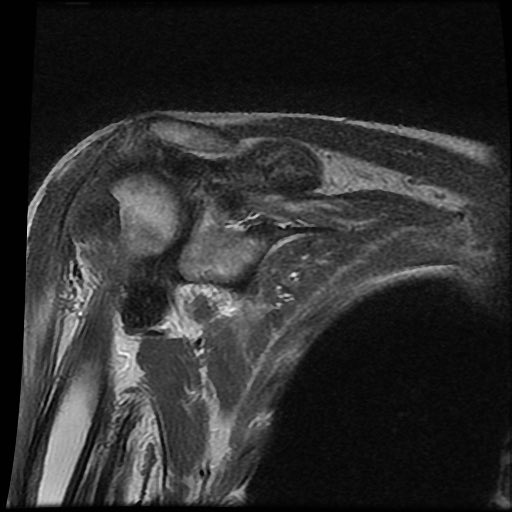

Chuỗi xung T2W

của bệnh nhân bị bệnh khớp do amyloid tại khớp vai.

Các

dấu hiệu bao gồm:

- Sưng nề trong khớp kích thước lớn do

lắng đọng amyloid giảm tín hiệu. - Lan rộng vào khoang dưới mỏm cùng vai và dưới vai.

- Bào mòn lớn tại chỏm xương cánh tay.

Tình trạng sưng nề phần mềm này không nên nhầm lẫn với các hạt cơm (rice bodies) như thấy trong

viêm khớp dạng thấp.